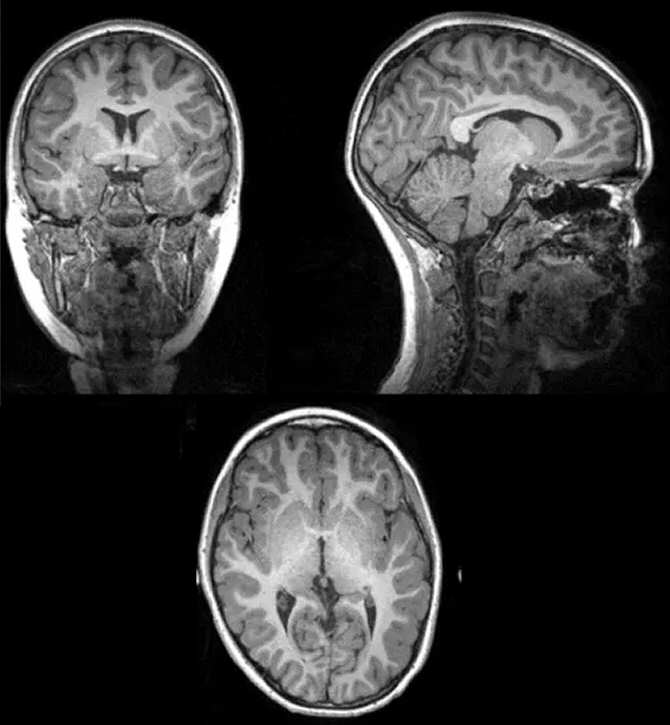

Ejemplo de imagen original de la resonancia magnética a partir de la cual los investigadores extrajeron la cantidad total de materia gris, materia blanca, y cantidad total cerebral. (Imágenes: UGR)

Este trabajo, titulado “Do fitter kids have bigger brains?” y publicado en la revista Scandinavian Journal of Medicine & Science in Sports, revela que los niños que fueron clasificados como “en forma” tenían mayor cantidad de materia gris, materia blanca, y en general, cerebros más grandes que aquellos niños que fueron agrupados como “en baja forma”. Asimismo, tener más materia blanca en el cerebro estaba relacionado con un mayor rendimiento cognitivo, concretamente, mayor flexibilidad cognitiva y función ejecutiva.

El trabajo demuestra que de entre los niños analizados, aquellos con mejor forma física tenían mayores volúmenes totales cerebrales que los niños con peor forma física.